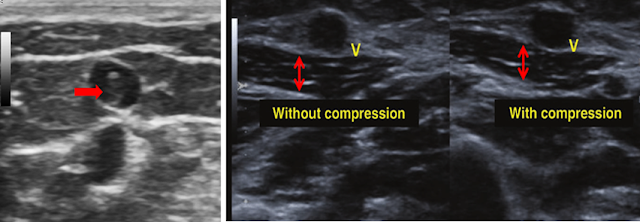

2. Multiple images of the distal radial vein were obtained using B-mode, M-mode ultrasound, and color Doppler. Comparative images of the proximal axillary vein were also provided, including compression views.

Ultrasound examination revealed that the superficial branches of the distal right cephalic vein were dilated and heterogeneous, showing diminished and turbulent flow.

Imaging Features

• Non-compressible vein

• Presence of intraluminal thrombus in the affected vein

• Reduced venous pulsatility

• Lack of vein expansion during the Valsalva maneuver

• Loss of Doppler flow signal